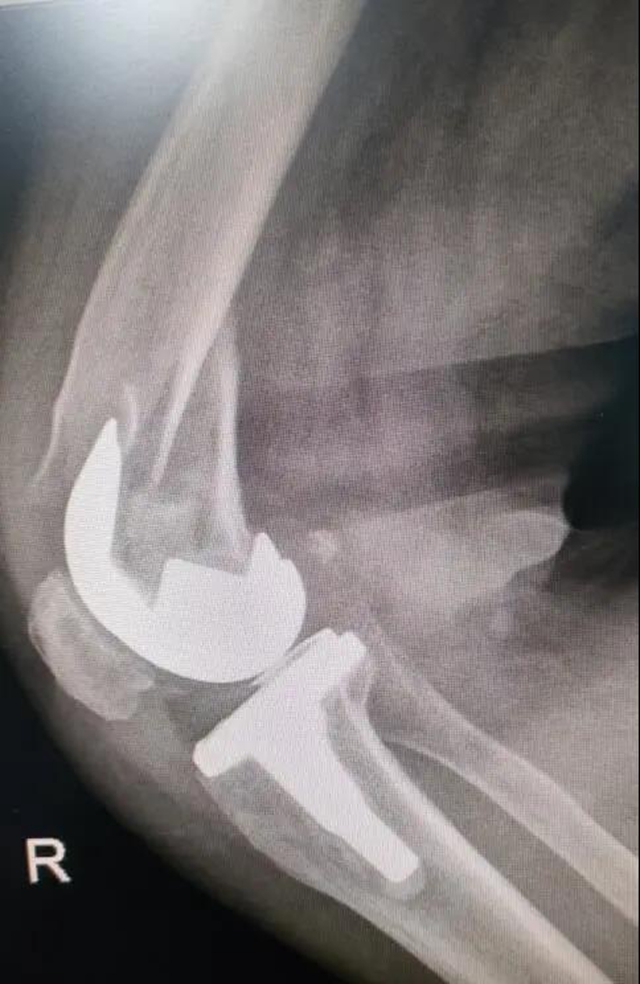

术前

家住龙马潭区的吴阿姨5年前因膝关节退行性病变在泸州市中医医院做了关节置换手术,术后逐步恢复正常行走及日常生活。

骨折部位在假体周围,患者还患有严重的内风湿、骨质疏松、高血压……能否耐受这台复杂而高难度的关节翻修与骨折手术?这对医院骨伤三科医护团队来说,是一个不小的挑战。